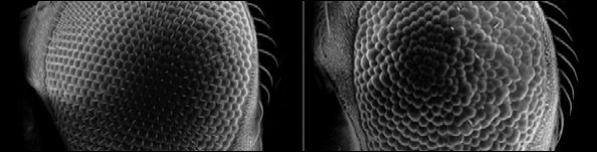

And while you can dissect a fruit fly to learn what's gone on; it isn't an easy job. Fortunately in this case you can gauge the extent of the interaction of the two human proteins by the amount of disorder caused in the eyes of the flies. You can see just this in this picture, normal fly on the left and disordered eye on the right.

Of course the physicist in me sees a simple experiment where you just get a load of flies to breed and then bung 'em in the scanning electron microscope for their eyeball close-ups. In fact my lack of experience with biological systems means I had completely forgotten that a major part of the research is breeding up a large population of flies with all the right genes in all the right places to work with in the first place.